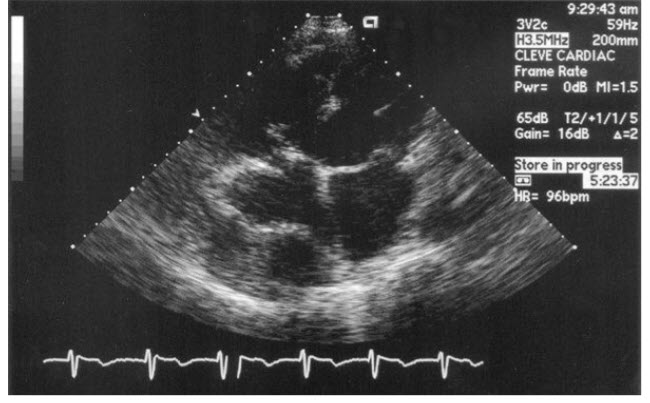

A 19-year-old male college student presents to his local physician for evaluation of a dry cough. His symptoms started 3 days ago but now appear to be resolving. He had planned a trip overseas but was concerned and is now seeking advice. His physical examination is unremarkable. A CXR is performed and is read as showing an enlarged right cardiac silhouette. A TTE is ordered, which is shown in Figure below.

The patient most likely has which of the following conditions?

He has a pericardial cyst that is benign; no further treatment should be offered. The TTE and CXR show a pericardial cyst. Pericardial cysts are usually smooth structures containing transudative fluid. They are frequently only 2 or 3 cm in diameter, often located at the right cardiodiaphragmatic angle, and clinically silent. However, cysts can be associated with chest pain, dyspnea, cough, and arrhythmias likely caused by compression of adjacent tissues. They can also become secondarily infected. In this patient, whose nonspecific symptoms appear to be resolving, no further treatment is needed.